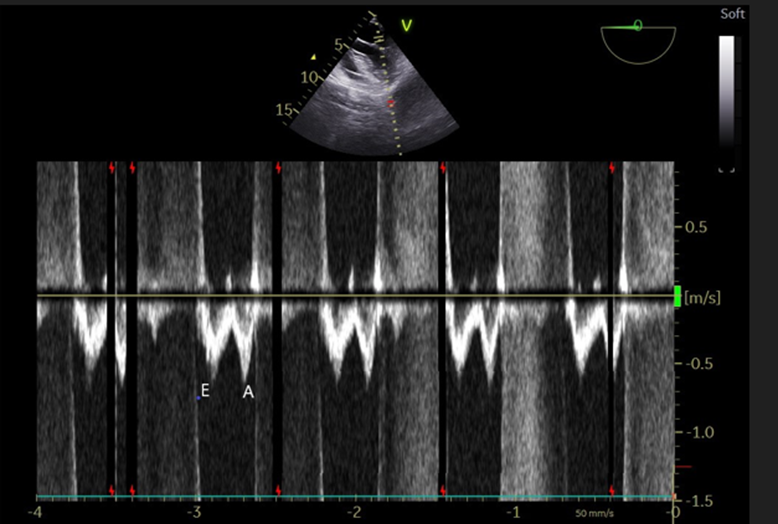

She was a patient of PIVD of the lumber region with a very heavy comorbidity burden including cardiovascular, respiratory and renal system. So, a thorough preoperative evaluation was required. Laboratory investigations revealed HB of 10.3gm%, total leucocyte count of 10260 cells/cumm, platelets of 2.43 lacs/cumm, HBA1c- 6.5%, total bilirubin/direct/ indirect were 0.2/0.1/0.1mg/dl respectively and SGOT/PT 20/12U/L respectively, ALP of 85 u/l, serum sodium/ potassium were 136/ 5.1 Meq /L respectively, total proteins were 5.65 gm/L, and serum calcium was 9.4 mg/dl, serum creatinine 1.43 mg/dl and blood urea 76.2 mg/dl and international normalized ratio(INR) was 0.97 and PT was 12.1 seconds. Electrocardiogram (ECG) showed LVH and LV strain (ST/T changes), and left bundle branch block (LBBB) (M pattern QRS) with frequent VPCs. [Figure-1] Chest X-ray AP view showed mild cardiomegaly with suspected focal lateral bulge arising from the left heart border suggestive of LV aneurysm. and normal lung fields. [Figure-2] she was not subjected to the breath-holding time and pulmonary function test due to a risk of fatal arrhythmias in the presence of severe cardiac disability. Even cardiac cath study and CT angiography to reveal coronary artery lesions could not be performed due to renal dysfunction, bronchospasm and low EF. Transthoracic echocardiography revealed Mild LVH, moderate mitral regurgitation, LV aneurysm and thinning of the posterior, inferior wall and at the basal segment, and akinesia of the basal, inferior and posterior wall, and hypokinesia of the inferior wall and a regional wall motion score index (WMSI) >1.7 suggestive of impending heart failure. In addition, EF was 30% and mitral inflow velocity revealed E > A, suggestive of grade 1 diastolic dysfunction and there was no thrombus in the LV aneurysm.

Figure-6: Mitral inflow velocity revealed E wave < A>

LV diastolic dysfunctions or heart failure with preserved EF( HFpEF) is called as diastolic heart failure with reduced LV relaxation or increased stiffness in the diastole that limits the proper filling of LV. Diastolic dysfunctions can be adequately assessed by TEE using the following parameters; mitral inflow velocity, mitral annular tissue doppler interrogation(TDI) for e’ and a’ prime, LA volume, TR velocity, pulmonary venous flow velocity.[48] The criteria to determine the severity of diastolic dysfunctions have been described in Table-3.[49,50,51] However, it’s not possible to provide the details of these diastolic dysfunction parameters in this current review. It has been reported that regional anesthesia or neuraxial block reduces the 0-30 days mortality in patients undergoing surgery with an intermediate or higher cardiac risk. [6] The important hemodynamic goals are to maintain MAP > 65 mmHg, low HR [60-70], and maintain SVR and contractility, sinus rhythm and normovolemia, and avoid tachycardia and myocardial ischemia. Treatment with beta-blockers or non-dihydropyridine calcium-channel blockers has been proposed to prevent tachycardia and improve LV diastolic filling. Patients with severe diastolic dysfunction may require more aggressive management, including inotropic support, vasopressors, or mechanical ventilation and TEE can be useful in early diagnosis and management of diastolic dysfunctions.[51] The lusitropic agents like calcium channel blockers, ACE inhibitors, inhalational agents or inodilators (milrinone, dobutamine, levosimendan) and NTG can be utilised to ameliorate the perioperative diastolic dysfunction. [53,54]

| Grade I (Impaired Relaxation) | E/A < 1> |